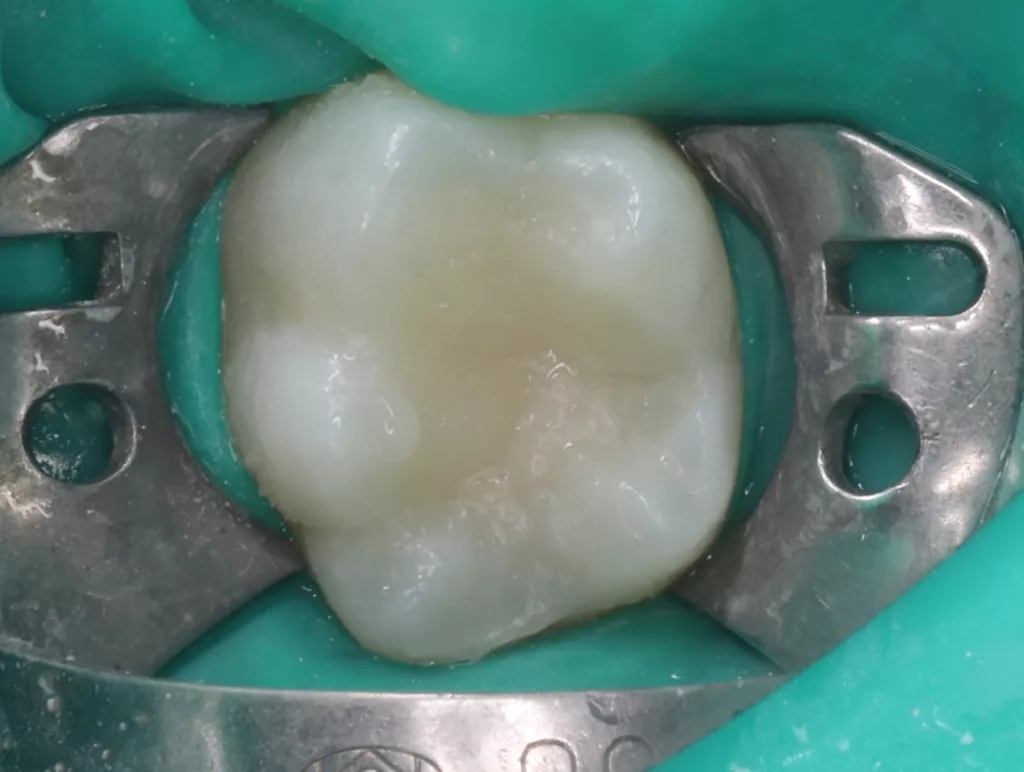

Bei routinemäßigen Röntgenkontrollen ergeben sich manchmal Zufallsbefunde unklarer Genese. So stellt sich beispielsweise bei der Betrachtung der Abbildung 1 die Frage, wie sich ein Zahnhartsubstanzdefekt so schnell entwickeln konnte. Ein weiteres Röntgenbild (Abb. 2), das vor dem Zahndurchbruch aufgenommen wurde, zeigt jedoch, dass es sich in diesem Fall nicht um Karies, sondern um die sogenannte präeruptive intrakoronale Resorption (PEIR) handelt. Für diesen Befund finden sich in der Fachliteratur auch noch andere Bezeichnungen wie „idiopathic external resorption of unerupted permanent teeth“ [1], „intra-follicular caries“ [2], „radiolucent lesions resembling caries“ [3], „occult caries“ [ 4] oder „pre-eruptive caries“ [5].

V. Slabkovskyi, O. LiutikovJahr vor dem Durchbruch des Zahnes 36.

Das fünfjährige Mädchen stellte sich 2017 zur jährlichen Routinekontrolle vor. Im Rahmen der Untersuchung wurden Röntgenaufnahmen der Milchmolaren gemacht (Abb. 2). Der klinische und radiologische Befund der vor uns früher gelegten Kompositfüllungen war gut, es wurde allerdings eine PEIR an den noch nicht durchgebrochenen ersten bleibenden Molaren festgestellt (Abb. 2). Den Eltern wurde empfohlen, sich unverzüglich bei Beginn des Durchbruchs der ersten Molaren erneut zur Behandlung vorzustellen. Ein Jahr später erschien die junge Patientin schmerzfrei zur Kontrolle. Der Zahn 36 war noch teilweise mit Gingiva bedeckt. Auf einer neuen Röntgenaufnahme (Abb. 1) wurde die PEIR-Läsion mit unveränderter Größe in pulpanahen Bereichen bestätigt (Grad 3 der Läsion nach Seow). Der Zahnschmelz sah intakt aus, es konnte kein pathologischer periapikaler Befund bei den noch nicht ausgewachsenen Zahnwurzeln festgestellt werden. Daraufhin wurden die verschiedenen Behandlungsmöglichkeiten von Fissurenversiegelung bis Vitalerhaltung der Zahnpulpa mit den Eltern des Kindes besprochen.